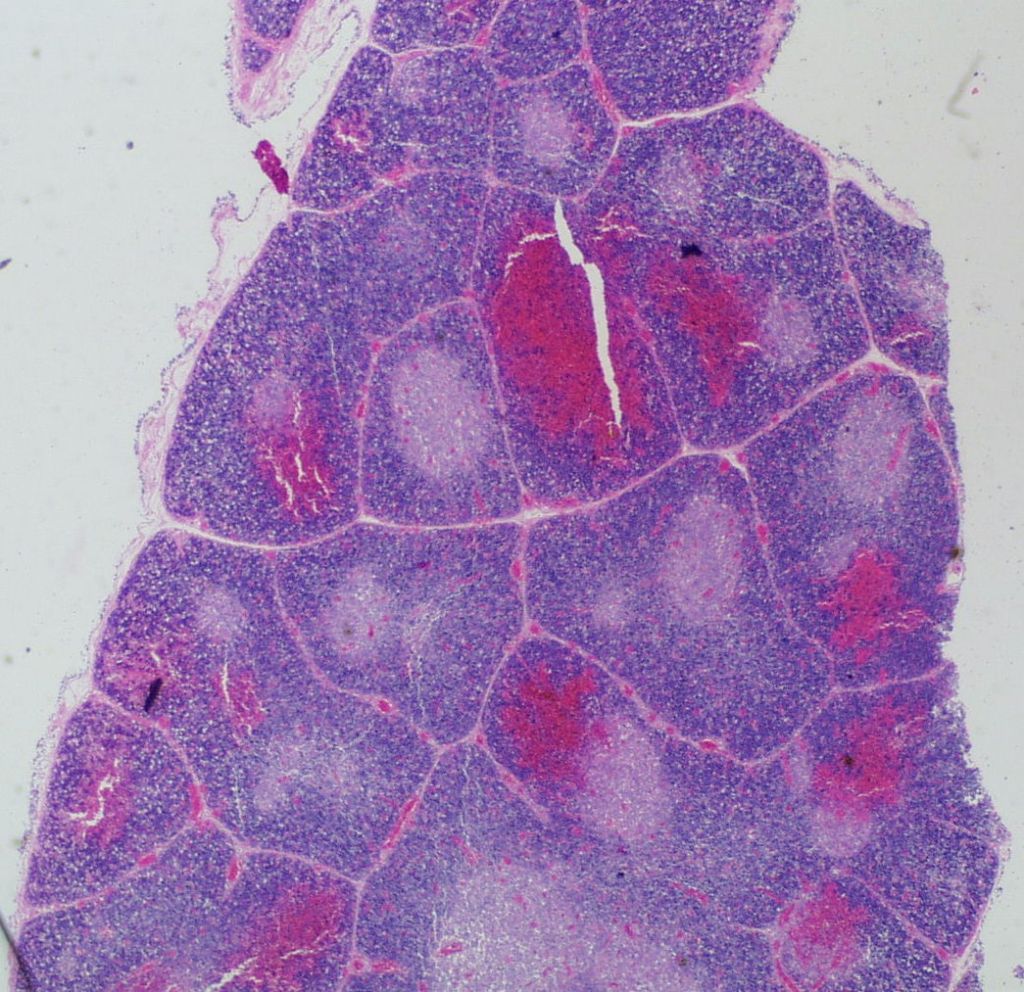

1. Petechial hemorrhages:

Petechial hemorrhages are usually scattered within the parenchyma, not just on the surface. (Fig 7,8)

They may be difficult to perceive in autolyzed tissue. Thymic petechiae have been associated with acute asphyxia in stillborn infants, such as with premature separation of the placenta[5, 6]. In this scenario, the petechiae are usually sparse, superficial, and as is also the case with thymic petechiae in SIDS, not on the cervical thymus. Larger, confluent hemorrhages in the thymus, often suggest a more systemic coagulation disorder. Thymic petechiae associated with asphyxia are often accompanied with other intrathoracic petechiae including on the visceral pleura and the epicardium. To interpret the meaning of these petechiae requires understanding the mechanism of petechial hemorrhage formation and then to relate that to the events that occur with acute intrauterine asphyxia.